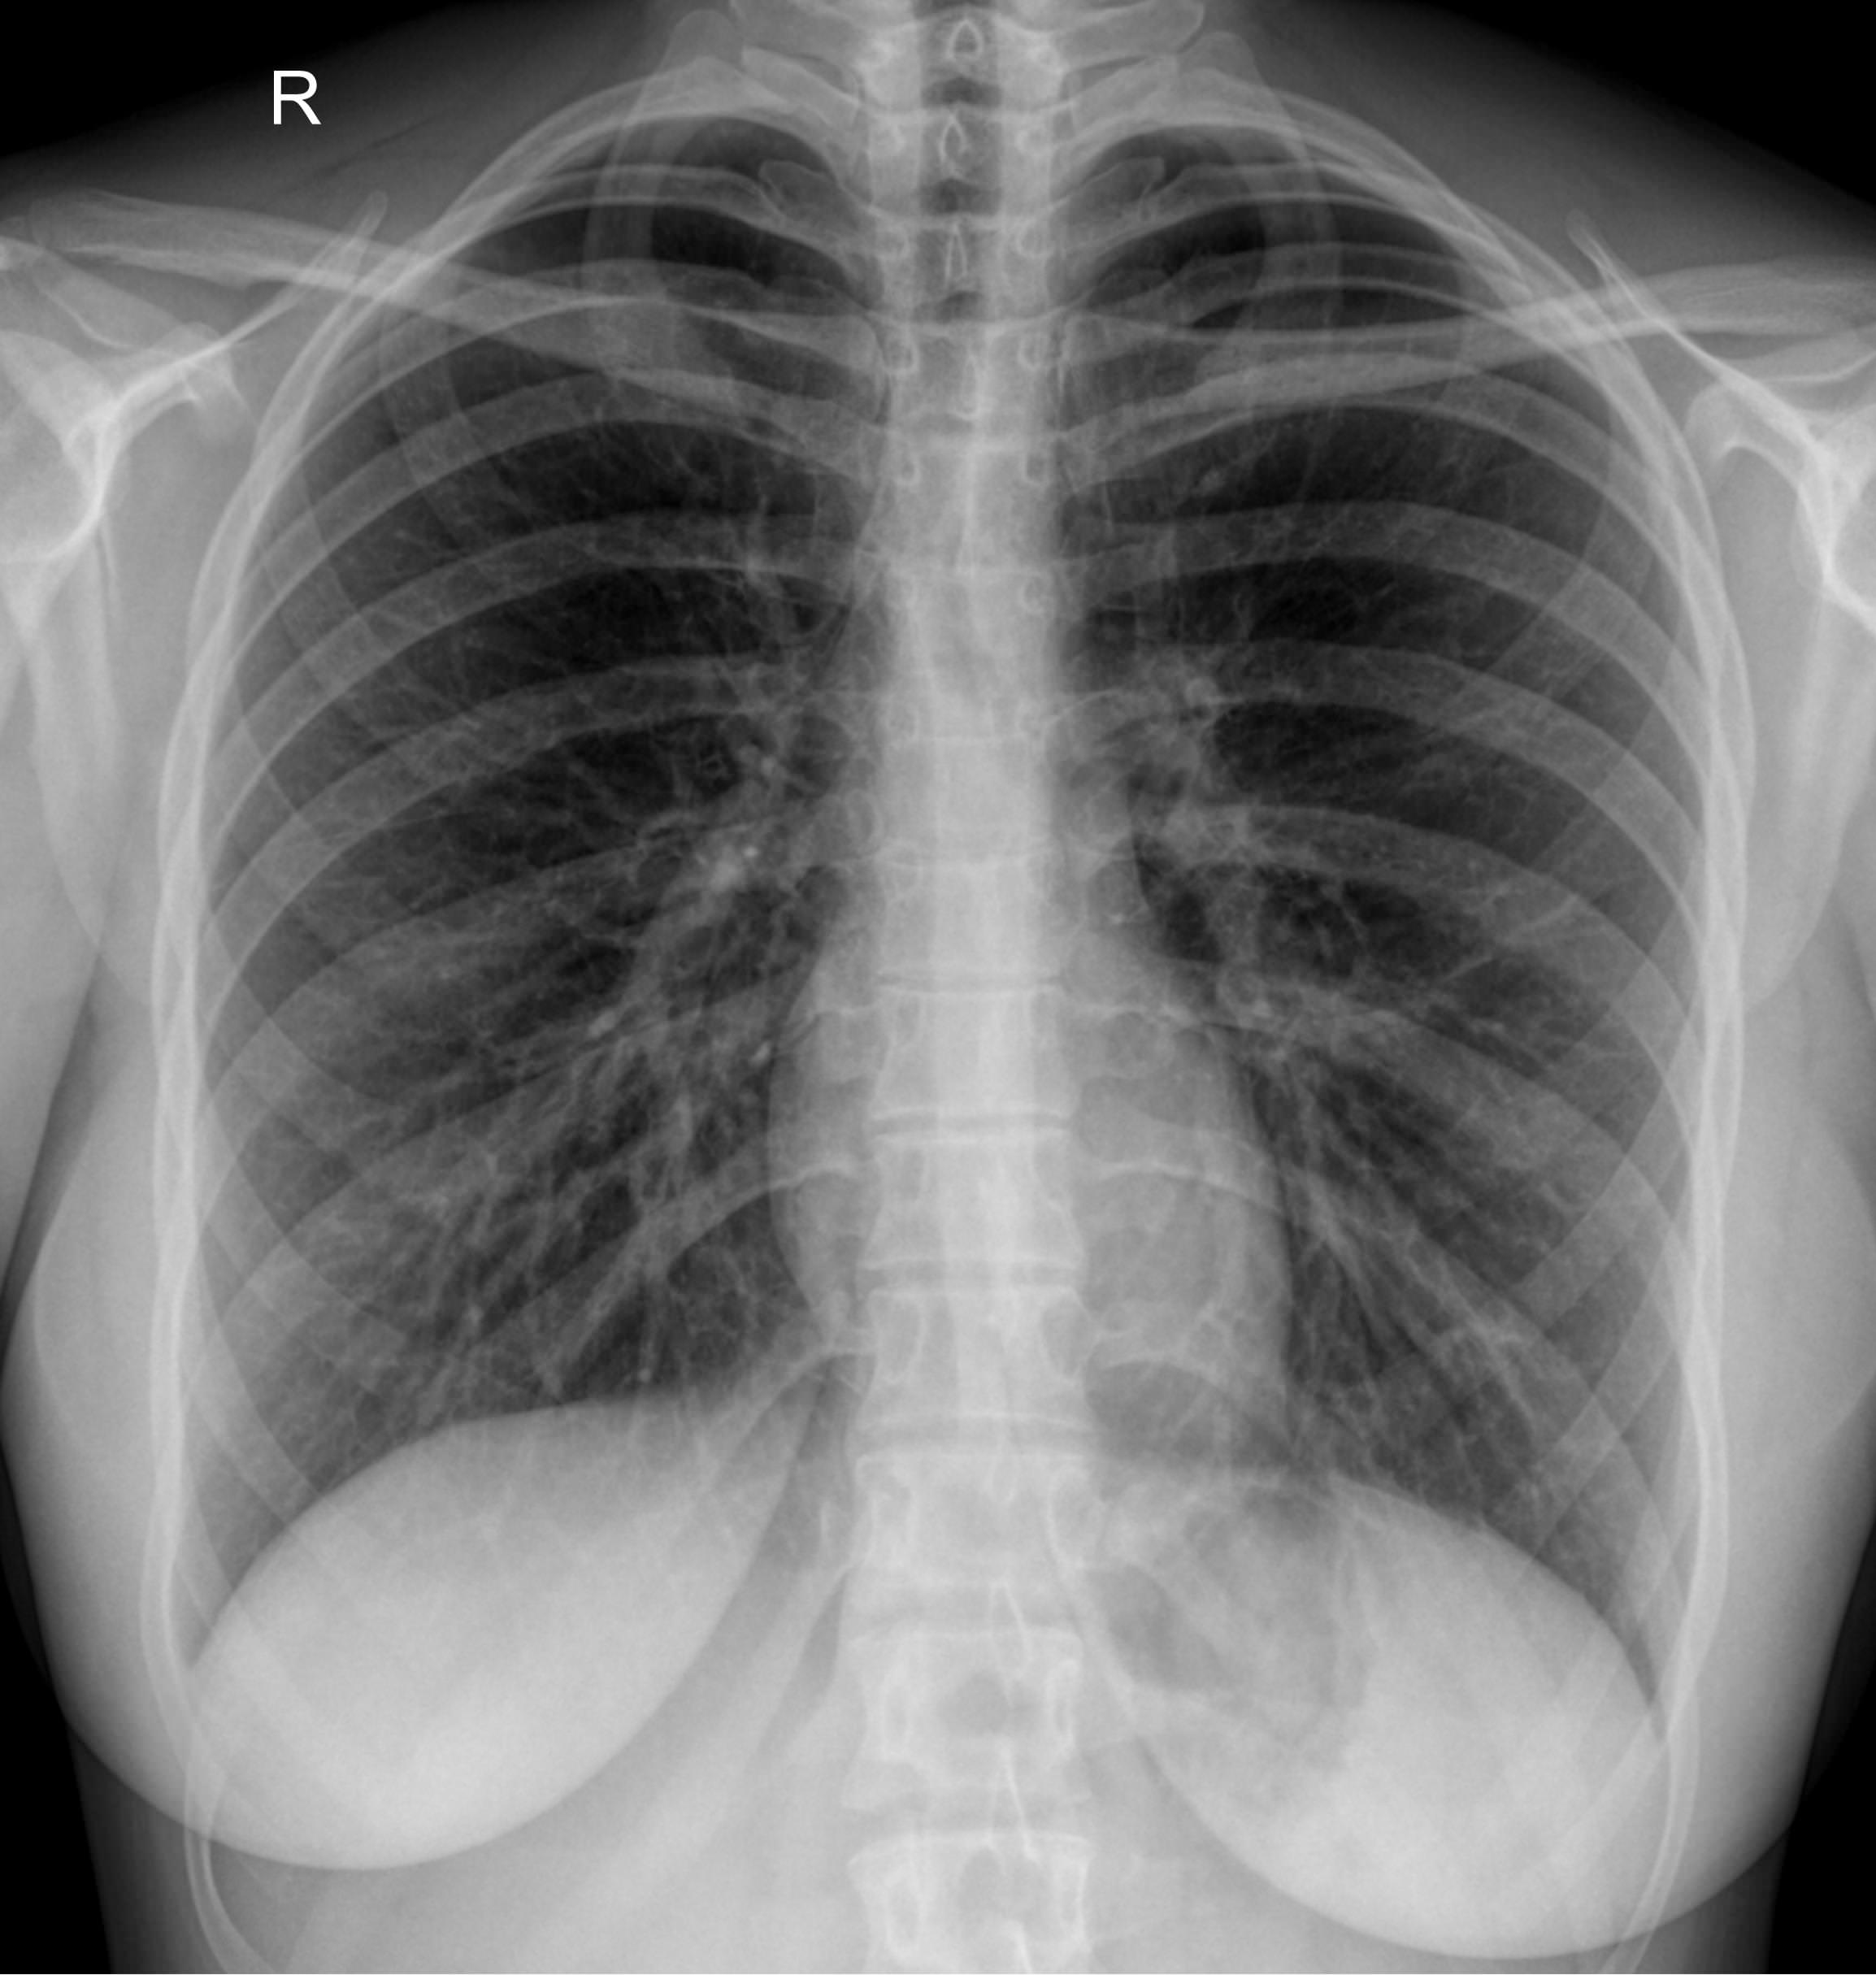

Диагностика с помощью рентгеновского излучения основана на его способности проходить сквозь живые и неживые объекты. В том числе, через тело человека. Органы разной плотности поглощают разное количество излучения, в результате на классическом негативном снимке наиболее плотные образования, кости, отображаются самыми светлыми, а наполненные воздухом ― почти черными. Мягкие ткани визуализируются как пятна серых оттенков. Участки, цвет и форма которых не типичны, говорят о патологии.

Снимок грудной клетки используют, чтобы получить изображение расположенных здесь органов: легких и дыхательных путей, контуров сердца с сосудами, а также позвоночника и костей. Обычно для диагноза достаточно одного снимка ― в прямой проекции, когда лучи идут сзади наперед. Иногда врач назначает снимок в боковой проекции, то есть слева или справа. Это необходимо, если требуется более точно определить сегмент поражения или достоверно исключить патологический процесс. Крайне редко требуются косые проекции, но они тоже бывают.

Что показывает рентген грудной клетки

На рентгенограмме видны следующие образования, расположенные в грудной клетке:

• Мягкие ткани: грудные мышцы, кожные складки;

• Костный скелет: ребра, ключицы, грудина, нечетко ― позвонки, в пожилом возрасте ― хрящи;

• Легочные поля: определяются их прозрачность, симметричность, легочный рисунок;

• Корни легких: топография, форма, структура, ширина;

• Средостение: положение сердца и сосудов, формирующих его дуги;

• Купол диафрагмы: четкость, местонахождение;

• Синусы: свободные или заполненные.